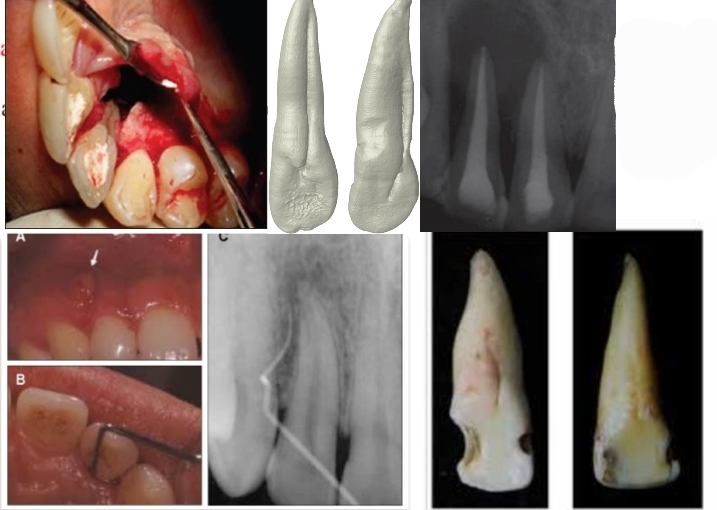

What are dilacerations?

Sharp bend in root - from trauma or bony interference during root formtation

Dilacerations

Why is Palatal groove a major cause of rct failure? Where is it found and what is its origin

Creates large permanent and irreparable periodontal bag - extraction needed

Is a developmental groove mainly found in maxillary lateral incisor lingual surface